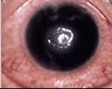

点状表層角膜症は、角膜の一番上にある上皮層の細胞が、数個から数10個単位で脱落してしまっている状態。いわば角膜の「スリキズ」です。酸素不足やレンズと角膜のまさつなどが原因で起こります。ほとんどの場合、自覚症状はありませんが、悪化すると角膜上皮の深い層まで脱落する「角膜上皮びらん」になってしまいます。

角膜上皮がはがれた状態(=びらん)。「点状表層角膜症」が悪化して発症する場合や、コンタクトレンズによる機械的な障害などが原因で生じる場合があります。また、「角膜浮腫」などほかの病気と合併することもあります。軽症では主に、異物感や目がしみるなどの症状があります。重症では激しい目の痛みや充血が起こり、まぶたが腫れることがあります。放置しておくと、「角膜浸潤」や「角膜潰瘍」にまで悪化してしまいます。

角膜にキズが生じ、角膜上皮と実質に炎症を起こしている状態。悪化すると、角膜上皮の一部がなくなり、もっと深い層までダメージが進んで「角膜潰瘍」になります。 通常、はげしい痛みや充血を伴いますが、ソフトコンタクトレンズでは自覚症状がない場合もあります。また、ソフトコンタクトレンズの場合、角膜上皮にキズがついても痛みが抑えられることがあるので要注意!知らないうちにキズが悪化し、「角膜潰瘍」になってしまうこともあります。

「角膜浸潤」がより悪化し、深いキズが角膜上皮から実質にまで進行してしまい、実質の一部が欠損した状態。激しい痛みや充血を伴います。角膜の上皮や実質の一部がはがれ落ちたりキズついたりすると、目のバリア機能が低下して、細菌やカビ、アカントアメーバに感染しやすくなってしまいます。感染症が起こると潰瘍がさらに悪化し、ときには失明の危険もあります。感染を伴った角膜潰瘍の多くは、ソフトコンタクトレンズ装用者にみられます。レンズケアで重要な“消毒”の過程が正しく行われていないために感染を起こし、角膜潰瘍を悪化させてしまうのです。